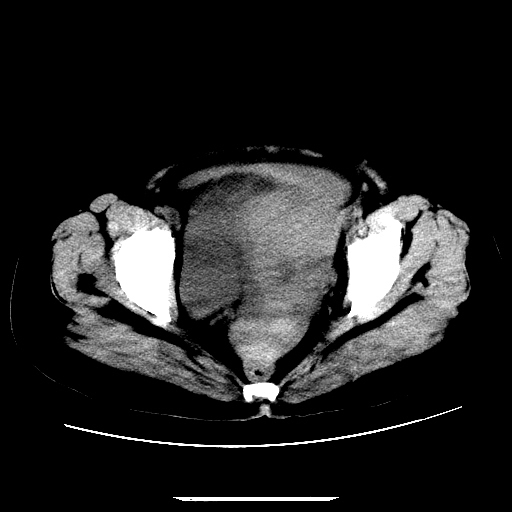

f,45y.怀孕4月晕倒,b超提示死胎,有手术结果,请展开讨论后明天告诉。

膈下-肠间隙内见气体密度影,子宫轮廓显示不清,宫腔-腹腔积液,首选考虑---子宫破裂出血。

1)宫腔妊娠。2)子宫破裂出血,腹腔及盆腔积血。

感谢同行们的高见。手术结果:子宫破裂出血。

我们的诊断是:腹、盆腔积液(考虑腹盆腔脏器破裂出血);宫腔妊娠。让人纳闷的是当时我们没有经验,现在回头看看分析:4月宫腔妊娠:1、洋膜囊不可能紧贴胎体这么小;2仔细看看子宫后壁肌层模糊不清;3腹、盆腔液体来源原因?4、45岁高龄妊娠有晕倒。由此可大胆诊断:宫腔妊娠子宫破裂出血。